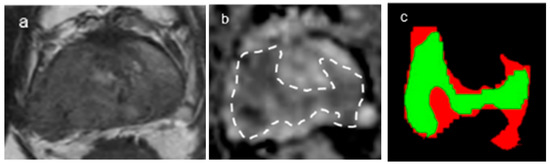

2.4. DL Architecture for Tumor and Gland Segmentation